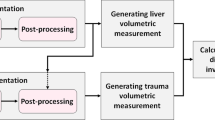

This retrospective study included adult patients with BHI between 1/1/2008 and 5/1/2017 from two institutions that underwent admission trauma CT prior to hepatic angiography (n = 73). Presence (n = 41) or absence (n = 32) of MHAI (pseudoaneurysm, AVF, or active contrast extravasation on DSA) served as the outcome. Voxelwise measurements of liver laceration were derived using an existing multiscale deep learning algorithm trained on manually labeled data using cross-validation with a 75–25% split in four unseen folds. Liver volume was derived using a pre-trained whole liver segmentation algorithm. LPDI was automatically calculated for each patient by determining the percentage of liver involved by laceration. Classification and regression tree (CART) analyses were performed using a combination of automated LPDI measurements and either manually segmented CE volumes, or CE as a binary sign. Performance metrics for the decision rules were compared for significant differences with binary CE alone (the current standard of care for predicting MHAI), and the AAST grade.

36% of patients (n = 26) had contrast extravasation on CT. Median [Q1–Q3] automated LPDI was 4.0% [1.0–12.1%]. 41/73 (56%) of patients had MHAI. A decision tree based on auto-LPDI and volumetric CE measurements (CEvol) had the highest accuracy (0.84, 95% CI 0.73–0.91) with significant improvement over binary CE assessment (0.68, 95% CI 0.57–0.79; p = 0.01). AAST grades at different cut-offs performed poorly for predicting MHAI, with accuracies ranging from 0.44–0.63. Decision tree analysis suggests an auto-LPDI cut-off of ≥ 12% for minimizing false negative CT exams when CE is absent or diminutive.

Current CT imaging paradigms are coarse, subjective, and limited for predicting which BHIs are most likely to benefit from AE. LPDI, automated using deep learning methods, may improve objective personalized triage of BHI patients to angiography at the point of care.